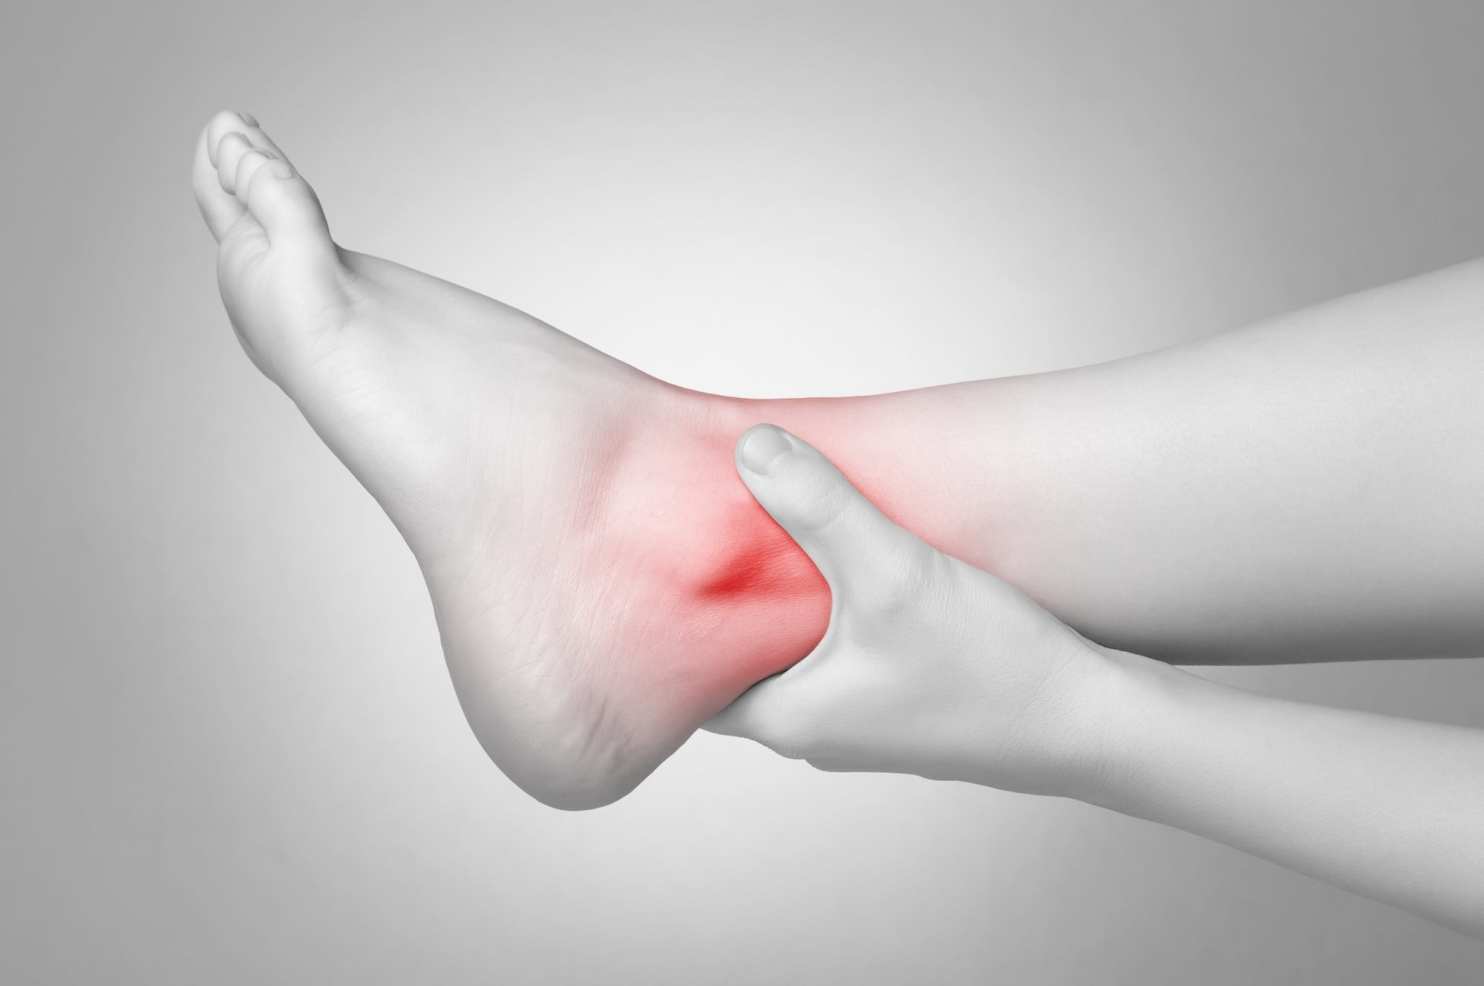

Хруст в голеностопе может быть симптомом практически любой воспалительной или дистрофически-дегенеративной патологии. Если он возникает на фоне болей, утренней скованности движений и припухлости сустава, то причиной крепитации стала деструкция костных, хрящевых или мягких тканей. Оттягивать визит к врачу нецелесообразно, так как все заболевания опорно-двигательного аппарата поддаются консервативному лечению только на начальной стадии. Что еще указывает на развивающуюся в голеностопе патологию: